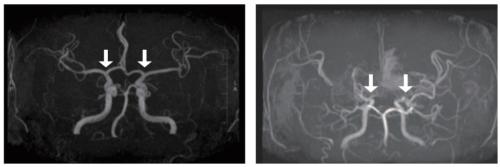

[»çÁø ¿ÞÂʺÎÅÍ] Á¤»ó ¹× ¸ð¾ß¸ð¾ßº´ ȯÀÚÀÇ ³úÇ÷°ü

Áö±Ý±îÁö ¸ð¾ß¸ð¾ßº´À» È®ÁøÇϱâ À§Çؼ­´Â ħ½ÀÀûÀÎ ³úÇ÷°ü Á¶¿µ¼úÀÌ Ç¥ÁØÀûÀÎ °Ë»ç¿´°í, À̴ ƯÈ÷ ¼Ò¾Æ¿¡°Ô Å« ºÎ´ãÀ» ÁÖ¾ú´Ù. MRI/A¿Í °°Àº ºñħ½ÀÀû °Ë»çµµ ÀÖÁö¸¸, Ç÷°ü ÇùÂøÀÌ °úÀåµÇ°Ô ³ªÅ¸³ª´Â °æ¿ì°¡ ÀÖ°í ³ú±âÀúºÎÀÇ ¸ð¾ß¸ð¾ßÇ÷°üÀ» ÀÚ¼¼È÷ Æò°¡Çϱ⠾î·Á¿ö Á¶±â Áø´Ü°ú Áúº´ÀÇ ÁøÇà »óŸ¦ Á¤¹ÐÇÏ°Ô ÆÄ¾ÇÇÏ´Â µ¥ ÇѰ谡 ÀÖ¾ú´Ù. ÀÌ¿¡ µû¶ó ¾×ü »ý°Ë(Ç÷¾× µî ü¾×À» ÅëÇÑ Áø´Ü)ÀÇ Çʿ伺ÀÌ ²ÙÁØÈ÷ Á¦±âµÇ¾î ¿Ô´Ù.